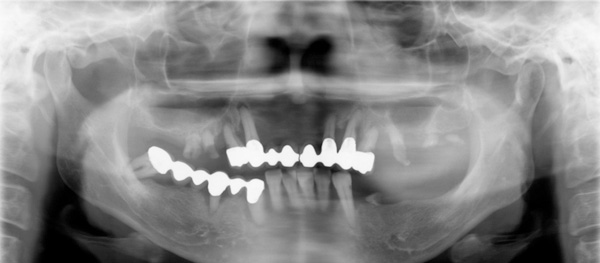

Before

フェイスボウトランスファーをおこない、中心位で咬合器につけました。咬合診断し、ポイントは咬み合わせの低下がみられたので、3㎜高くしました。